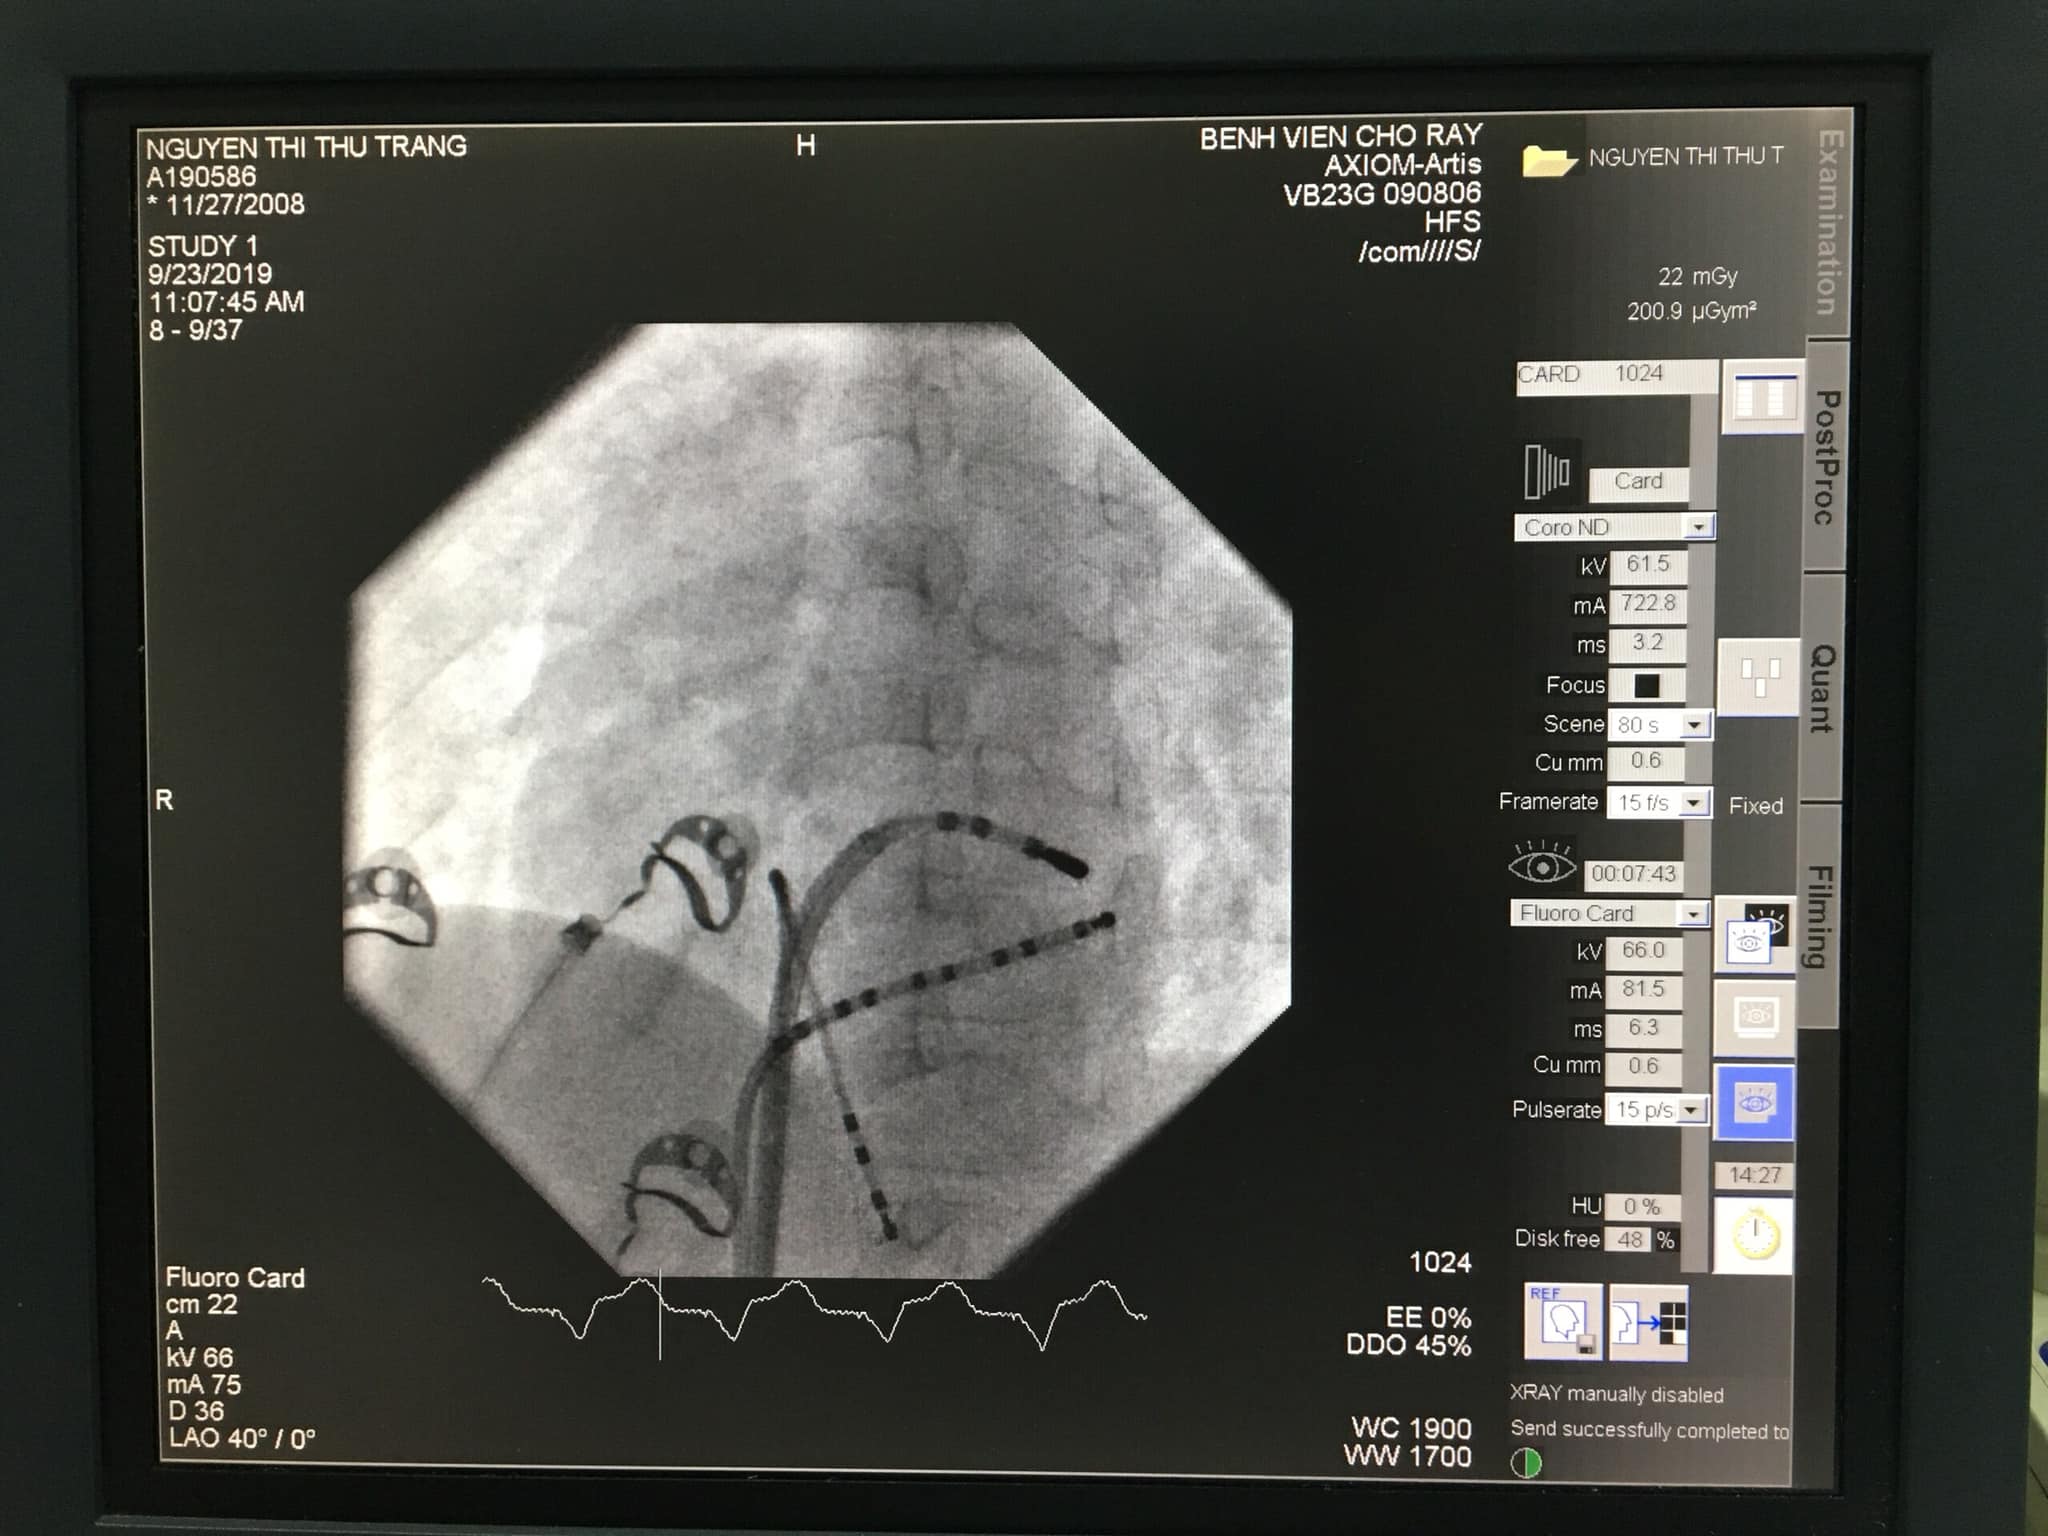

Sau khi xác định chẩn đoán, bệnh nhi được chỉ định can thiệp cắt đốt bằng sóng cao tần (radiofrequency catheter ablation) nhằm triệt phá đường dẫn truyền phụ gây rối loạn nhịp.

Do bệnh nhi còn nhỏ, thủ thuật đặt ra nhiều thách thức trong việc lựa chọn đường tiếp cận mạch máu và kích thước dụng cụ can thiệp.

Sau hơn 2 giờ thực hiện thủ thuật, các bác sĩ đã triệt phá hoàn toàn bó cơ bẩm sinh gây loạn nhịp (Concealed Bundle of Kent).

Vị trí đường dẫn truyền phụ được xác định tại thành trước bên của vòng van hai lá (anterolateral mitral annulus), vị trí khoảng 2-3 giờ.